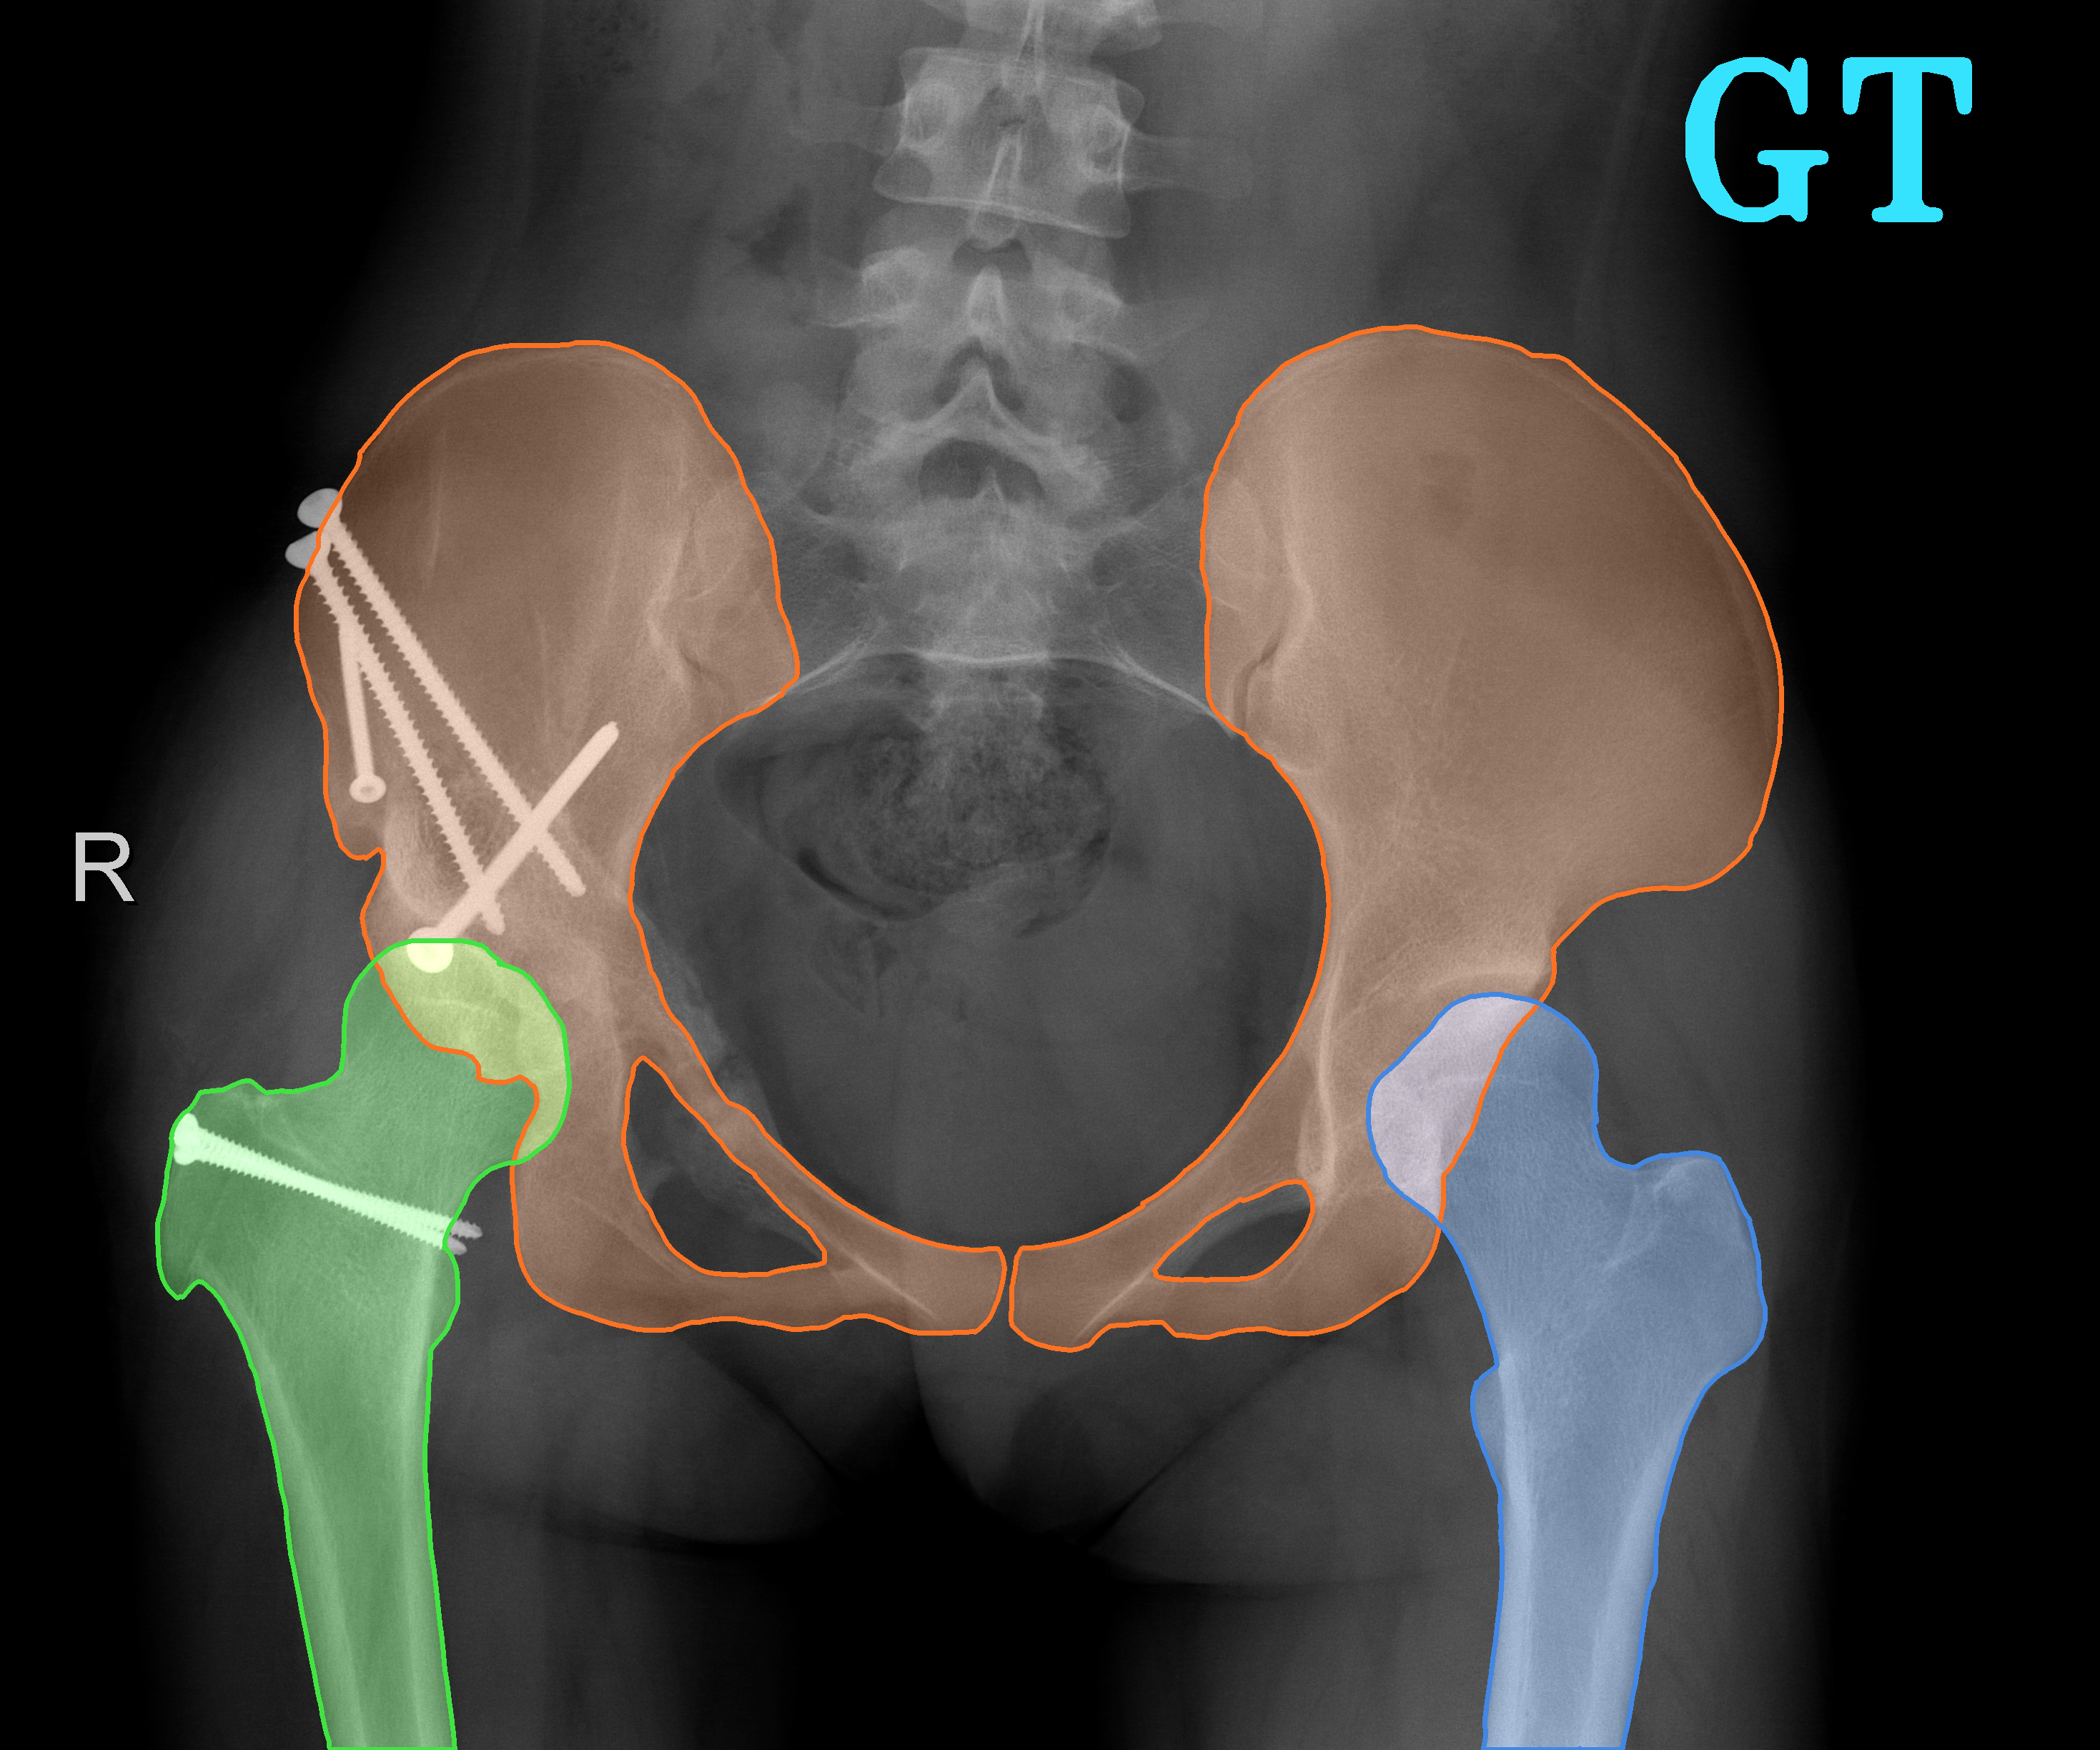

TransFuse is evaluated on both 2D and 3D datasets to demonstrate the effectiveness. As different medical image segmentation tasks serve different diagnosis or operative purposes, we follow the commonly used evaluation metrics for each of the segmentation tasks to quantitatively analyze the results. Selected visualization results of TransFuse-S are shown in Fig. 2.

Results of Hip Segmentation. Tab. 3 shows our results on hip segmentation task, which involves three human body parts: Pelvis, Left Femur (L-Femur) and Right Femur (R-Femur). Since the contour is more important in dianosis and THA preoperative planning, we use Hausdorff Distance (HD) and Average Surface Distance (ASD) to evaluate the prediction quality. Compared to the two advanced segmentation methods [33, 28], TransFuse-S performs the best on both metrics and reduces HD significantly (30% compared to HRNetV2 as well as 34% compared to Unet++ on average), indicating that our proposed method is able to capture finer structure and generates more precise contour.